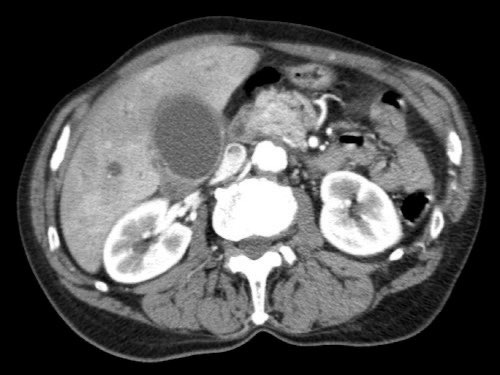

Tái tạo mặt phẳng coronal cho thấy:

- Bất thường bờ viền thành SMV được nhận thấy rõ hơn trên tái tạo coronal này (mũi tên).

- Khối u ở thân tụy (đầu mũi tên trắng).

- Huyết khối trong các nhánh bên của SMV (mũi tên xanh nhỏ).